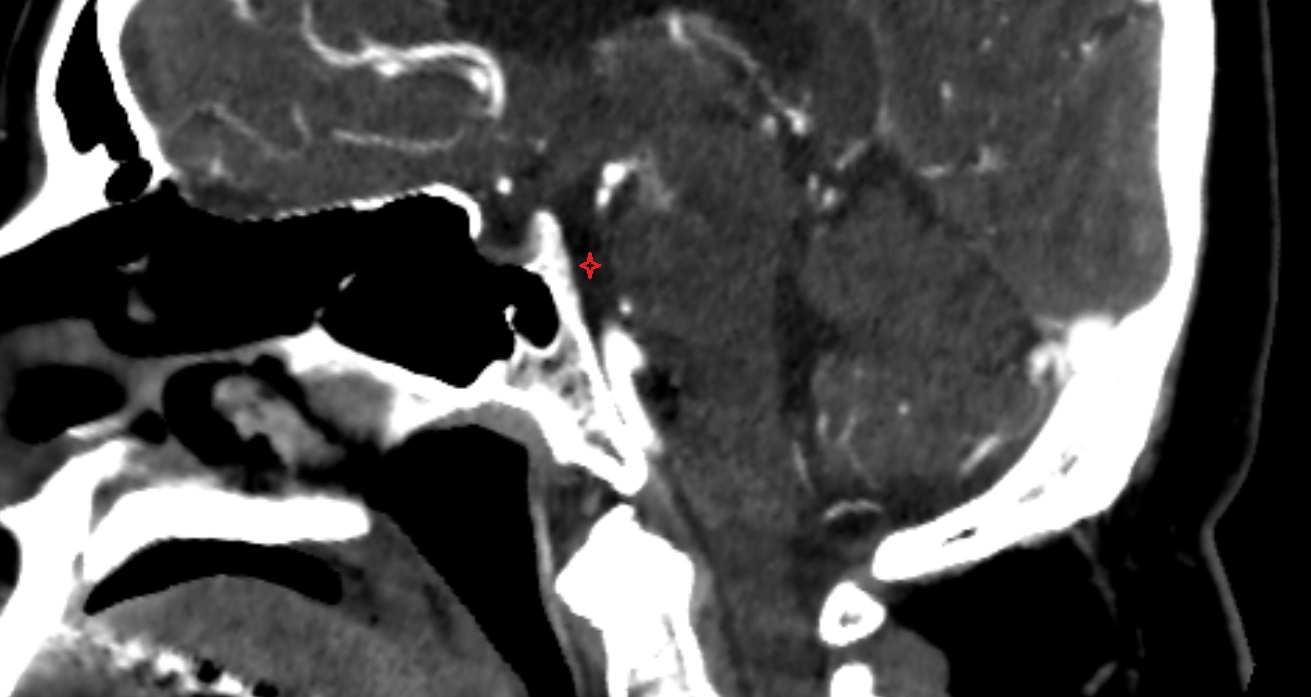

- Meckel’s cave (Trigeminal cave)

- Trigeminal cave

- Trigeminal ganglion

- Trigeminal nerve (Cranial nerve V)